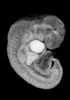

MRI Slice Selector

Mouse: click on a line below to select a view

Finger: tap a line below with a very light touch